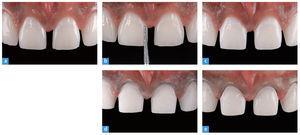

El acabado y el pulido de la preparación son el requisito para obtener unos modelos precisos. Este paso de trabajo se lleva a cabo con un diamante fino, serie roja (n.º 8856 018, Brasseler). Éste posee la misma forma y el mismo diámetro que la fresa utilizada durante la preparación. El acabado de la preparación elimina todos los rasguños de la fresa previamente empleada (fig. 18). En la figura 19 se ofrece una vista detallada de la preparación extremadamente respetuosa. Tras el acabado se utilizan de nuevo las llaves de silicona para verificar la preparación (fig. 20). Los caninos se pulen únicamente para eliminar eventuales zonas retentivas que pudieran obstaculizar el ajuste de las carillas parciales.

Fig. 18. La preparación pulida terminada.

Fig. 19. Tomas de detalle de la preparación de carilla extremadamente respetuosa. a Vista de los dientes anteriores superiores centrales antes de la operación; b el rebajado de la altura proximal de la forma; c después del rebajado proximal; d el inicio de la reducción; e la preparación terminada tras el pulido.